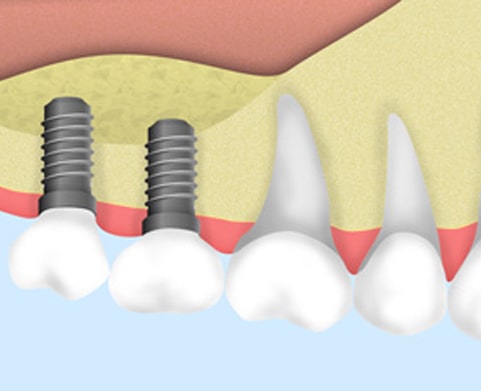

インプラント治療とは、歯を失った箇所に人工の歯根(インプラント)を埋入し、歯を補う治療法です。

一次手術

あごの骨にフィクスチャー(歯根部)を埋め込みます。

局部麻酔で行うため痛みはほとんどありません。入院の必要もありません。

約1週間程度で抜糸や消毒を行います。個人差がありますが、3~6ヶ月程度の安定期間をおきます。フィクスチャー(歯根部)と骨が結合する、大切な期間です。

二次手術

上部構造(人工歯)を取り付けるためのアバットメント(土台)を装着します。

歯茎が少ない場合は歯茎の移植をする場合がございます。

人工歯の装着

歯ぐきが安定したら、上部構造(人工歯)を取り付けます。